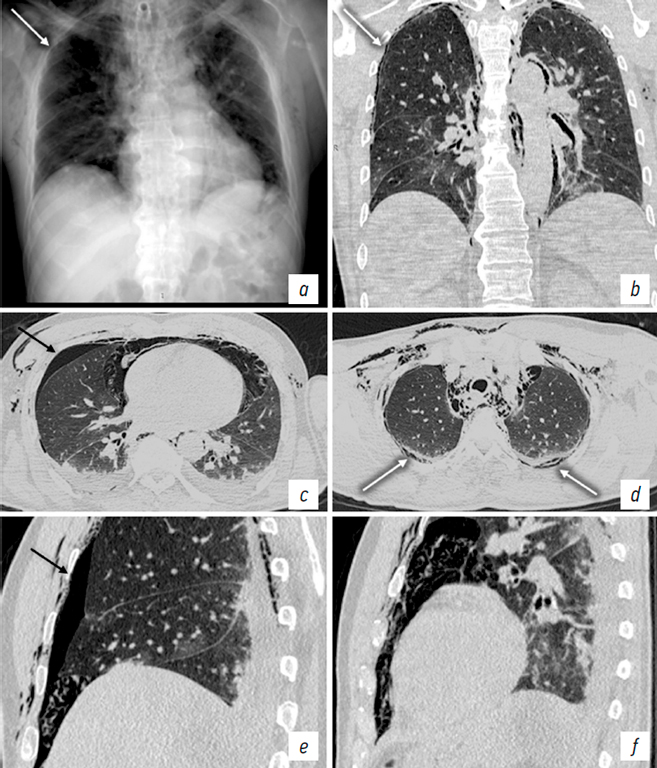

Furthermore, unilateral coexistence of pneumothorax and EPS emphysema was observed in five patients (Fig. 6). In three of these patients, the drainage tube was positioned in the EPS, which resulted in failure to drain the pleural cavity, progressive clinical deterioration, and the development of subcutaneous emphysema (Fig. 7). In one case, severe EPS emphysema was associated with respiratory failure (Fig. 8). US revealed findings characteristic of pneumothorax, including the absence of pleural sliding (Fig. 9).

Fig. 6. Patient M. a, chest X-ray in the anteroposterior view. Chest CT: b, coronal plane; c, d, axial plane at different levels; e, sagittal plane through the right hemithorax; f, sagittal plane through the left hemithorax. Right-sided pneumothorax (black arrows). Pneumomediastinum. Bilateral extrapleural emphysema (white arrows).

Рис. 6. Пациент М. a — рентгенограмма органов груди в прямой проекции. КТ органов груди: b — фронтальная плоскость; c, d — аксиальная плоскость на разных уровнях; e — сагиттальная плоскость через правый гемиторакс; f — сагиттальная плоскость через левый гемиторакс. Правосторонний пневмоторакс (черные стрелки). Пневмомедиастинум. Эмфизема ЭПП с обеих сторон (белые стрелки).